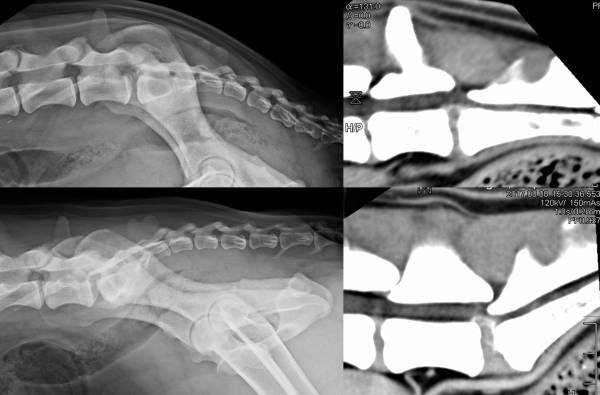

- Röntgen: Hüftbeugung und Hüftstreckung

- CT / MRT